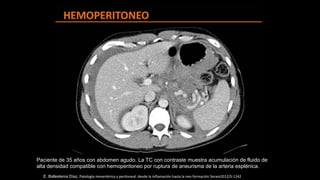

Paciente de 35 años con abdomen agudo. La TC con contraste muestra acumulación de fluido de

alta densidad compatible con hemoperitoneo por ruptura de aneurisma de la arteria esplénica.